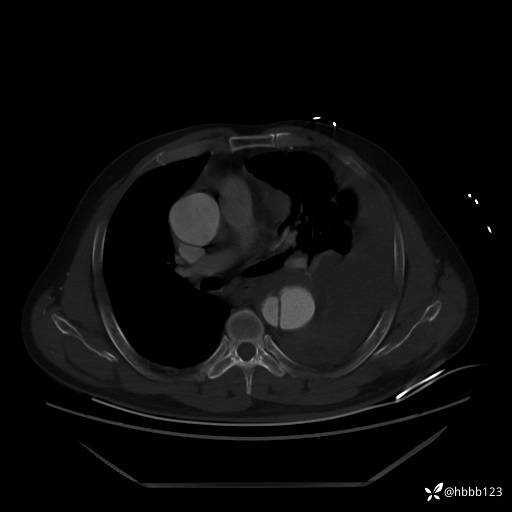

急查胸腹主动脉CTA:

(为方便观察,调至骨窗)